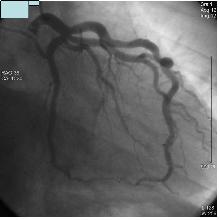

#. ɱ̶ٰ ?

- ⱸ 뵿ƿ ̶ ϸ (ɱ) ȴ. ¸ Ȱ ϱ Ͽ ȯŰ ü ̳ ҳ Ҹ ƾ ϹǷ װ ſ ߿ϴ. ο ǰ ϰ Ǹ ɱ ¿ ̸ Ǵµ ̷ ȯ ̶ Ѵ.

ƿ ưȭ ǰ ̿ Ͽ ü, ưȭ öũ Ŀ̳ ־ Ϻΰ , ɱټ ܵǾ ( ) Ű ɱ̶ٰ մϴ. ۺ а, 帶 縦 ʷ ɼ ϴ. ȯ ȯ 50-70% ź ϰ ִ ȭǾ ̰, 15-20% ϴ ִµ ̴ ַ 索 ȯڳ , ε Ÿ ִ.

#. ɱٰ ? - 漺 Ǵ ȭ̴, ߸ ̷ ħ ϰ ǰ ӵǸ ڲ Ǯ ó ϴ ħ ܴ Į ȴ. ̷ ǰ ɱٿ Ǵ Ͽ, 䱸 Ȳ Ұ ɱ Ÿ ȴ.

ɱ , ִ ưȭ ջ ް ǰ ӿ ִ ǰ ̿ پ Ƕ̶ Ҹ ϰ Ǹ ɱ װ Ǿ ɱ 翡 ̸ ȴ.

ɱٰ Ǵ ưȭ ݵǴµ, ӵ ־ , , , 索 ȴ. , , ݷ ưȭ 3 ڶ ϸ ̷ 3 ̿ܿ ռ 索, , , Ʈ ưȭ Ų.

ۿ ü ̳, ƿ, 뵿 Ǹ ȯ ȯ ִ.

#. ɱٰ

- ũ Ҿ 2 ִ. 쿡 հ Ѱ Ȥ ȣϴ 찡 ȯڴ ̰ йϴ 谨, ̴ , ſ, , ¥ , Į Ȥ , ǥѴ. Ȥ , , , , , ް ĵǸ, δ ȣ, Ƿΰ, , ǽ ȣϴ 쵵 ִ. ̷ Ȱ üȰ, , Ļ , ۽ ( ҿ ߿ ̵ ), 踦 ǿ ƹڼ ϰų л 쿡 Ÿ ȴ. ̶ Ÿ Ͻ(2-15)̾ ϸ 3-5 , Ʈα۸ ϸ 밳 1 ̳ ɴ´. 20 30 ̻ ӵǴ , ӽð 5 ̳̰ų, ȣ , ϴ , ҵǴ , ̳ ҵǴ , 2cm , ؾ ̴. Ҿ ı ϳ ɱٰ ̿ ġѴ. ɱٰ ȯ 30-60% Կ Ҿ Ѵ. ÿ ϰ, ӵǰų Ƚ Ʈα۸ ϴ 츦 Ѵ.

ٸ ִµ ̴ Ȥ ̸ ħ ȣϰ ǰ Ʈα۸ Į .

ɱٰ ϳ 30 ̻ ξ Ÿµ, ̸鼭 ϰ Ÿ Ǵ ٰ ϸ ġ ϴ Ȳ ǥȴ. Ȱ üȰ, , Ļ , ۽ ( ҿ ߿ ̵ ), 踦 ǿ ƹڼ ϰų л 쿡 Ÿ Ǹ ӽð 30 ̻ ӵȴ. ̶ Ʈα۸ ؿ ־Ƶ ʴ´. ̳ , ̱ Ͽ ǰ ʿϴ. Ư 索 ΰ ִ ȯڿ ߺϱ ϹǷ ʾ 찡 .

ɱٰ ȯ 밳 ܰ ġḦ Ѵ. ϴ ݺǸ Ǹ ã ϰ ˻縦 ƾ Ѵ. ⺻ ˻δ ݷ ˻, ɱȿ ˻ ִ. Ư ̵ ˻縦 ı ϴ ſ ߿ϴ. Ҿ ɱȿ ġ ST δٸ ST ɱٰ ﰢ ʿϴ. ɱȿ ġ ST ST ɱٰ̳ Ҿ ﰢ Կ ġᰡ ݵ ʿϴ.

ǽɵ ˻, 24ð Holter ˻, (Ȥ ) ˻, ˻ ̿Ͽ ϰ ȴ. ֱٿ CT˻縦 3 ̰ ִ.

- CT -

Ȯ ˻ Ÿ Ȥ ȸ ̿Ͽ úα ġŰ Ͽ , Ȯϴ ̴.

- -

#. ɱٰ ġ - ȯ ġῡ , Ϲݿ, , ü ִ. ưȭ ų ִ ġῡ ݵ ݵǾ Ѵ. Բ ǥ ü ϵ ϰ, ڴ ݵ 踦 Ѵ. ΰ Ͽ 帶 30-40 ˷ ִ. . 索. ̵ ȯ ġ ȯ ġ 濡 ſ ߿ϴ. ݷ δ ¡, Ұ, , , 븥, , ǥ̸ ̵ 븦 ϰ Ĺ⸧ , , ⸧ ȭ 븦 ø ٶϴ.

Ϲ . ù°, ü Ȱ ϸ ־ ȯڰ Ҿ ϹǷ Ͽ ϵ Ѵ. ħ. ȭ Ƿ ħ̳ Ļ Ŀ ӵ ٵ, 2ð ̻ ¿ Ѵ.

δ 꿰, Ÿ-Ƶ巹 ü , Į, ƽǸ ִ. ﰢ ʿ ɱٰ ִ. ð ߿ѵ 2ð 3ð ̳ ȿ ݵ ݱ ִ Ȯϰ ϴ ߿ϴ.

üġ Ÿ Ȥ ո Ͽ dz dz Ȯ κ а ϴ Ȯ (Ʈ) ־ ְ ϴ Ʈ Լ Ѵ. ̴ Ͽ ϴ ġῡ 밡 ʿ 밳 üð 1~2ð ̸̳ Ư ݼӸ ߵ ġ ſ ֱ θ Ǵ ġ̴.

üġ ذ ȯ Ͽ ų ̽ϴ ƿȸ ؾ Ѵ.

ȯ ġĢ 캸 켱 ġḦ ϰ Ȯ˻ ߰ߵ ݼӸ Լ Ѵ. ı ϰ Ȯ ؾ ϸ Ư ɱٰ ִ Ȥ Ȯ ݼӸ Լ Ѿ Ѵ.